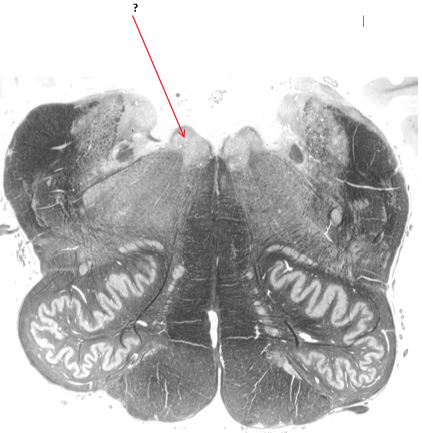

Name this.

Fourth ventricle.